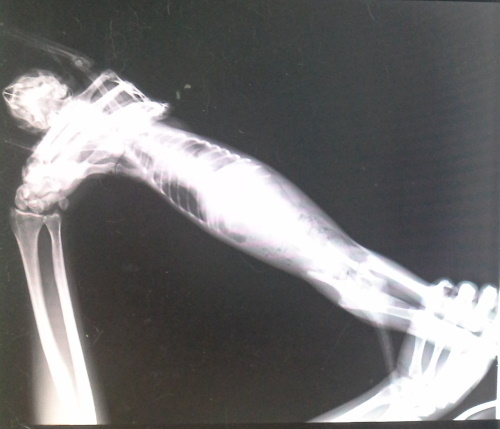

主題: 貓咪求助醫療協助 申請者姓名: 郭崑杉 花色: 申請日期: 2014-08-05 14:36:35 申請者部落格: 申請者臉書網址: 所在縣市/合作醫院: 新竹市/新竺動物醫院 治療費用: 17950元 需求人數: 20人 已結案 (2014-11-12 11:48:35) 報名人員: Patrick x2(已付款)、Wendy Kao(已付款)、JuJu x4、JuJu x2、JuJu x3、JuJu x3(已付款)、Ivy Hsu(已付款)、lavinia x2(已付款)、Ed Tsai x2(已付款)、peiyu(已付款)、Bella Hung(已付款)、chiawei(已付款)、薛、薛(已付款)、Bow Huang x2(已付款)、Fionna Hsu x2(已付款)、胡衿綾(已付款)、 候補人員: 動物病情說明: 這隻白灰貓咪呼吸非常急促,本來以為是鼻氣管炎,7/17送醫治療,貓咪偏瘦,喘,鼠蹊處瘀血,貓瘟檢驗陰性,Xrays顯示胸腔有異物,懷疑橫膈赫尼亞肝臟進入胸腔中,且血檢肝指數偏高,小貓精神食慾非常好,擔心但時間拖久了對貓咪不利,於7/28手術,術中發現肝臟在胸腔中,已有黏連狀況發生,雖然手術順利完成,但因為胸腔的壓力改變,身體無法負荷於術後死亡。